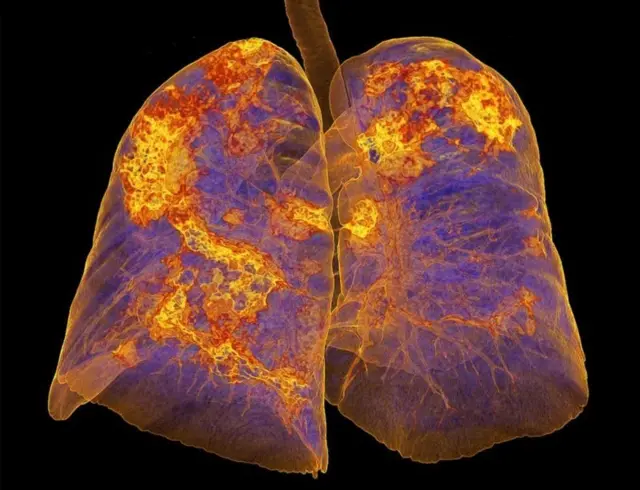

কোভিড-১৯ নামের এই রোগে প্রধানত ফুসফুস আক্রান্ত হয়।

বক্ষব্যাধি বিশেষজ্ঞ ডা. রওশন আরা খানম বিবিসি বাংলাকে বলছেন, ''করোনাভাইরাসে আক্রান্ত হওয়ার পর যাদের হাসপাতালে ভর্তি হতে হয় বা আইসিইউতে যেতে হয়, তাদের ফুসফুসের ক্ষতিটা বেশি হয়। তাদের সেই ক্ষতি কাটিয়ে উঠতে, স্বাভাবিক জীবনযাপনে যেতে অনেক সময় লেগে যায় বলে আমরা দেখেছি। তাদের জন্য পরবর্তীতে 'ফুসফুসের পুনর্বাসন প্রোগ্রাম' দরকার হয়ে পড়ে।''

বক্ষব্যাধি বিশেষজ্ঞ ডা. রওশন আরা খানম বলছেন, করোনাভাইরাসে আক্রান্ত হলে মানুষের শরীরে অনেক সময় অক্সিজেনের স্বল্পতা তৈরি হয়। ফুসফুসের কার্যক্ষমতা কমে যাওয়ার কারণেই এটা হয়।